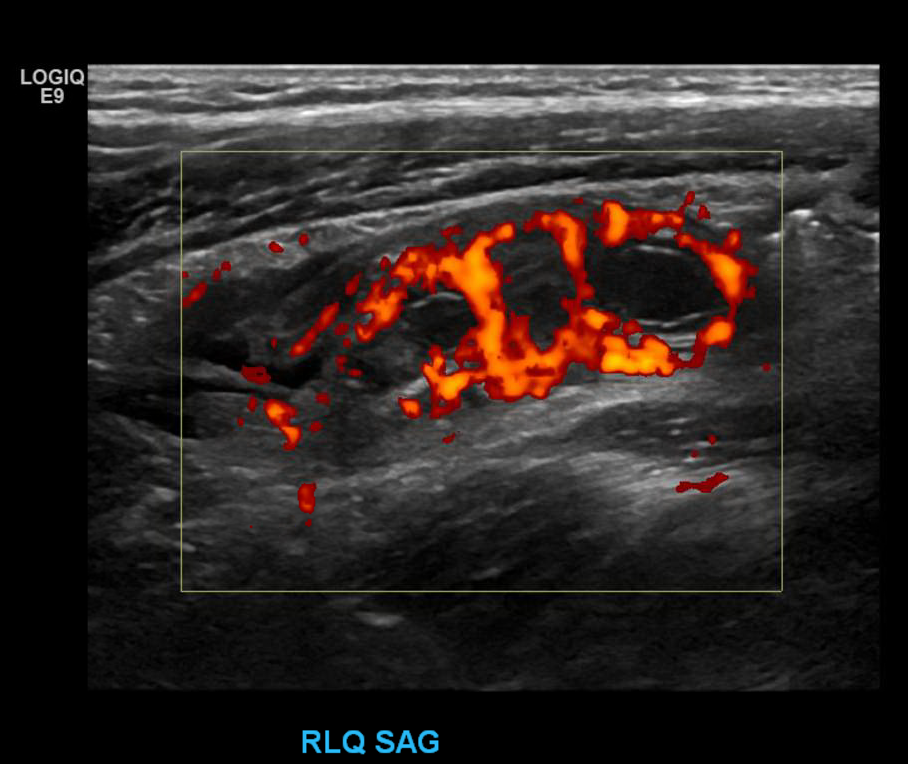

Appendix Ultrasound